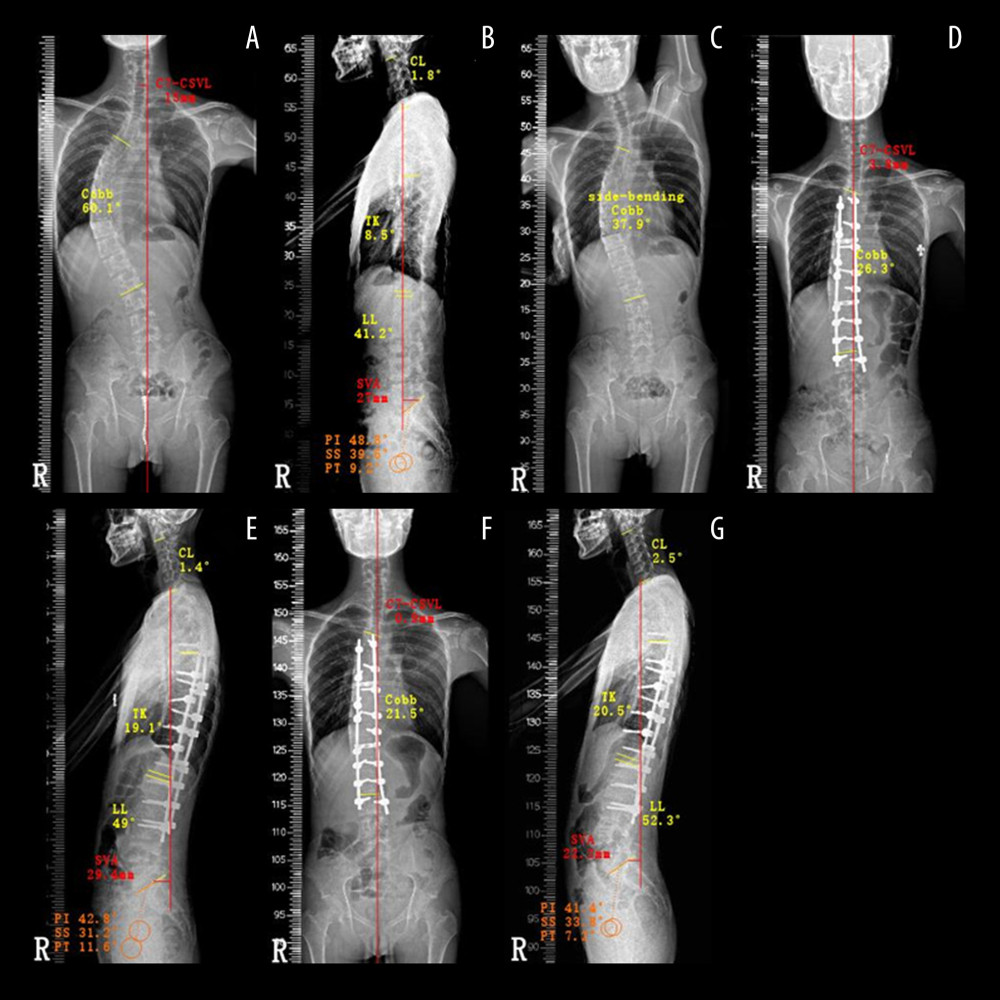

Scoliosis Imaging What Radiologists Should Know RadioGraphics Plumb Line Scoliosis A plumb line is dropped vertically from the center of the c7 vertebral body. Adult spinal deformity is an idiopathic or degenerative condition of the adult spine leading to a deformity in the coronal or. The c7 plumb line is a radiographic reference to determine the sagittal vertical axis, the most traditional measurement of sagittal balance of the spine. Adolescent. Plumb Line Scoliosis.